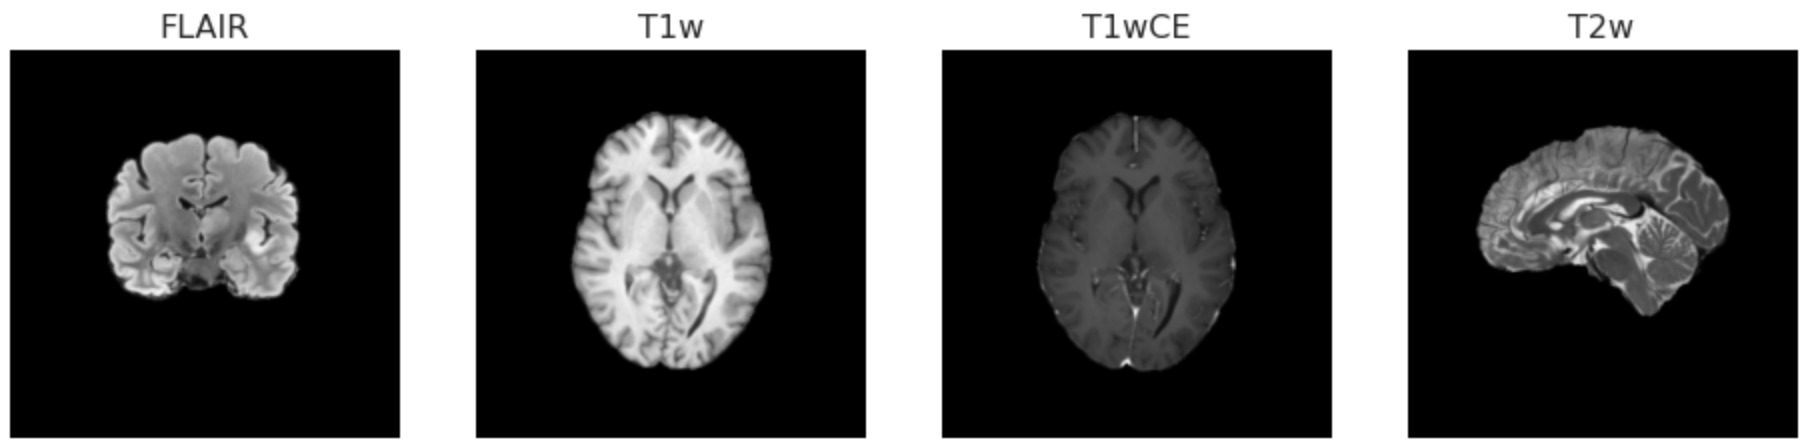

The radiogenomic classification task dataset contains multi-parametric MRI (mpMRI) scans for 585 patients with glioblastoma. Patients fall into two categories based on their MGMT status: methylated MGMT (1) and unmethylated MGMT (0). The dataset is evenly distributed across the two classes, with 307 methylation cases and 278 unmethylated cases, as shown in Figure 1(a). As a result of the balanced nature of the dataset, the learning algorithm is not expected to show skewing behavior. In addition, metadata such as modality, orientation, and MRI machine-specific information are included in the Digital Imaging and Communications in Medicine (DICOM) header of the images. Images have variable slice thicknesses ranging from 0.43 to 6 mm. Four imaging modalities are used to capture each patient’s images: T1-weighted pre-contrast (T1), T1-weighted post-contrast (T1wCE (Gadolinium)), T2-weighted (T2), and T2 Fluid Attenuated Inversion Recovery (T2-FLAIR). Each of these MRI modalities highlights a different aspect of the target area which, when used together, can assist in better localizing the tumor region than can one modality alone. Table 1 depicts the differences between the MRI modalities.

The number of slices for each patient differs across the modalities mentioned above. Patients with the IDs [00109], [00123], and [00709] are excluded from the dataset because the quality of their images is unacceptable and we do not want them to affect our analysis. Furthermore, MRI scans come in three orientation planes, including coronal, axial, and sagittal. Figures 1(b) and 1(c) display the distribution of scans among various MRI modalities and orientations, respectively. The different scan modalities for some patients were saved in the same orientation plane, but not for all patients. Figure 2 shows four random slices for two patients displaying the four modalities and the existence of the same and different orientations for different patients within the dataset.